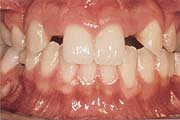

Wann machen Implantate Sinn?

Einzelzahnersatz

Gesunde Nachbarzähne müssen nicht beschliffen werden. Eine

unauffällige und natürliche Lösung. Anspruchsvoll in

der Ästhetik und langfristig im Nutzen.